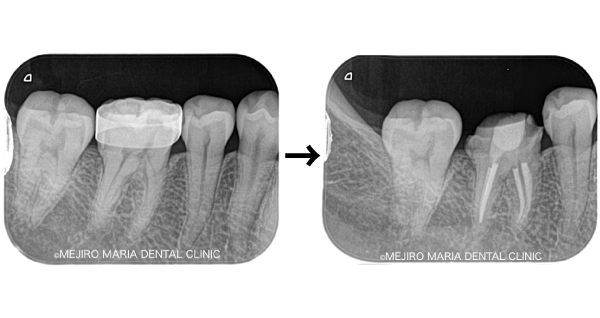

歯科用拡大鏡、歯科用顕微鏡下にて、軟化象牙質(虫歯)を除去後、歯髄を確認すると一部の歯髄には血流がなく部分壊死を起こしていることがわかる。

今回は術前に歯髄炎による疼痛を確認していたため、水酸化カルシウムを貼薬した後、2回目の治療にて根管充填、支台築造処置を終了させている。

|歯の寿命を左右する初回根管治療_術前術後のレントゲン画像比較-1024x756.jpg)